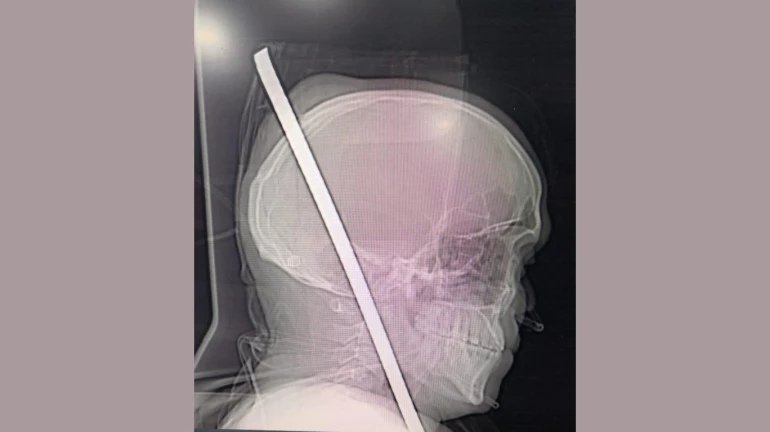

मंगळवारी २० नोव्हेंबर रोजी चेंबूरजवळील उंच इमारतीचं बांधकाम सुरू असताना अचानक १३ फुटांवरून तोल जाऊन राकेश जाधव खाली पडला. तोल गेलेल्या राकेशच्या छातीत ३ फूट लोखंडी सळी घुसली व ती थेट त्याच्या डोक्यातून बाहेर पडली. बराच रक्तस्त्राव झाल्यानं त्याला वाचवणं अशक्य होतं. परंतु प्रसंगावधान राखून काही कामगारांनी राकेशला जवळच्या झेन रुग्णालयात दाखल केलं.

रुग्णालयात दाखल करण्यात आल्यानंतर झेन रुग्णालयातील न्युरोसर्जन डॉ. बटुक डिओरा, डॉ. प्रमोद मस्जीद, डॉ. प्रमोद काळे यांसह इतर डॉक्टरांच्या मदतीन त्याच्यावर शस्त्रक्रिया करण्यात आली. ५ तासाच्या गुंतागुंतीच्या शस्त्रक्रियेनंतर त्याच्या छातीत घुसलेली लोखंडी सळी काढण्यात आली. ही शस्त्रक्रिया यशस्वी झाल्यानं राकेशचा जीव वाचवण्यात रूग्णालय प्रशासनाला यश आलं.